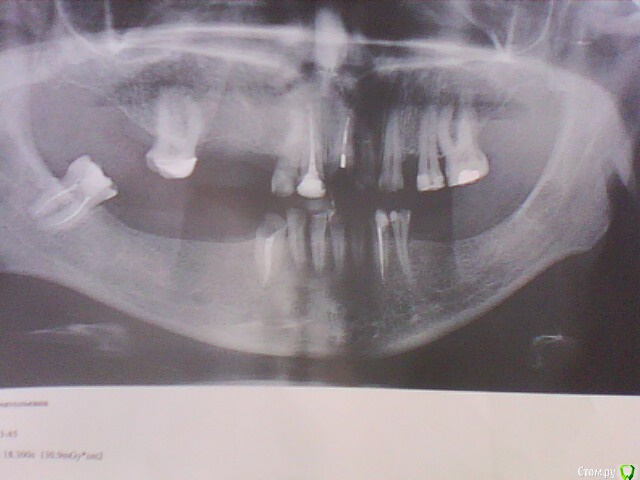

ОльгаS Опубликовано 16 декабря, 2014 Автор Поделиться Опубликовано 16 декабря, 2014 (изменено) Будет удален передний корень, где сломан штифт, и верхняя правая шестерка - под вопросом, но сама склоняюсь к тому, что бы ее сохранить, один их предложенных мне специалистом вариантов - 2 импланта, верхняя челюсть, и 4 - нижняя, в другой клинике предложили, удалить шестерку, тогда 3 импланта - верхняя, и 5 - нижняя, какой вариант все же более оптимален, мне самой, естественно, не определиться, да и как, если один специалист заявил, что слева в нижней челюсти близко расположен челюстно-лицевой нерв и имплант он там ставить не будет, а установит два и сделает один зуб подвесным, т.е. будет мостик, клиники обе - бизнес-класса. Изменено 16 декабря, 2014 пользователем ОльгаS Ссылка на комментарий

ОльгаS Опубликовано 16 декабря, 2014 Автор Поделиться Опубликовано 16 декабря, 2014 Оба раза на консультации присутствовали и имплантолог и ортопед, добавлю еще снимки: Ссылка на комментарий